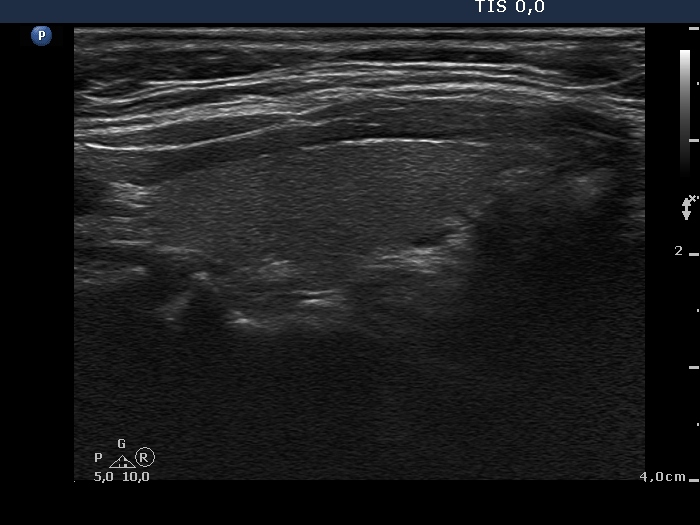

100 consecutive cases of papillary cancer - case 042 (ultrasonographic picture 6)

Left lobe, longitudinal scan.